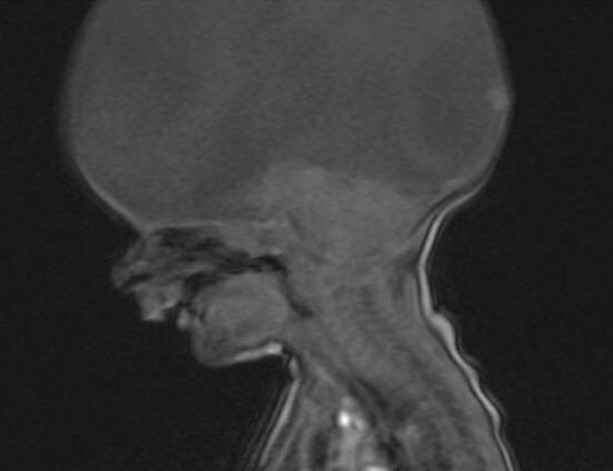

图片均来自网络男孩生下来就没有大脑,医生劝诫放弃,可男孩的父母却让事情发生了扭转!而他的父母也诠释了什么叫做“生命的坚强”!在荷兰,一对夫妇生下了一位天生无脑男孩,这样的噩耗确实给这对夫妇带来了承重的打击和心痛!

在男孩2岁的时候,夫妇俩发现男孩根本不能动也不能讲话,便将男孩带去医院检查!检查结果显示,男孩依旧还是无脑孩子,医生告诉夫妇俩,他们的儿子每日的存活是没有大脑意识的,就像是行尸走肉,医生劝解夫妇俩让男孩安乐死!